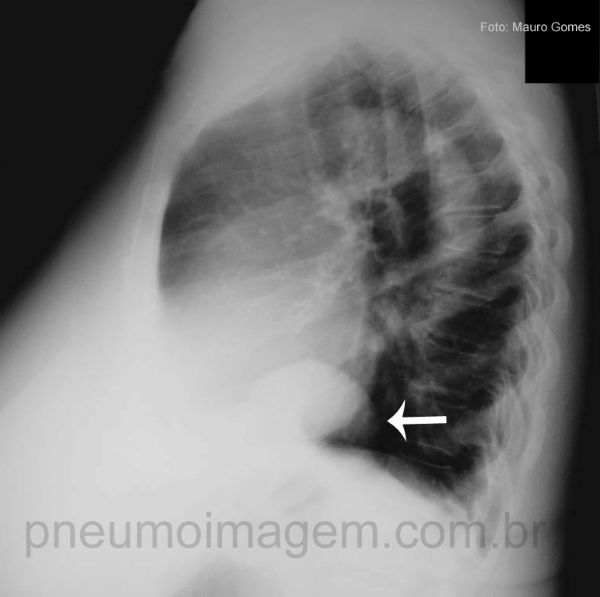

A Eventração Diafragmática (seta) é a elevação total ou parcial da cúpula do diafragma associada à perda de mobilidade, sem rompimento do músculo. Pode ser adquirida através de lesões do nervo frênico (traumas torácicos fechados, lesões iatrogênicas pós-cirúrgicas, tumores torácicos ou infecções) ou congênita (anomalia do desenvolvimento diafragmático muscular centrípeto).

The Diaphragmatic Eventration (arrow) is the total or partial lifting of the diaphragm associated with loss of mobility, without disruption of the muscle. It can be acquired through the phrenic nerve injury (blunt chest trauma, post-surgical iatrogenic injuries, thoracic tumors or infections) or congenital (anomaly centripetal diaphragmatic muscle development).

Vista ao perfil, a Eventração Diafragmática (seta) não pode ser confundida com a Hérnia Diafragmática (herniação do conteúdo abdominal para a cavidade torácica através de abertura anormal no diafragma).

The Diaphragmatic Eventration (arrow) can not be confused with Diaphragmatic Hernia (herniation of abdominal contents into the chest cavity through an abnormal opening in the diaphragm).